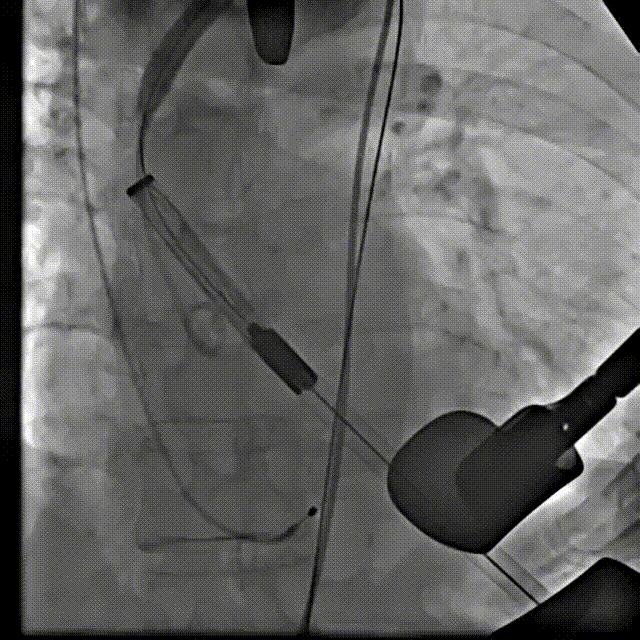

主动脉根部造影

18 mm球囊预扩张

输送系统到位

瓣膜交界对齐释放

22 mm球囊后扩

最终造影